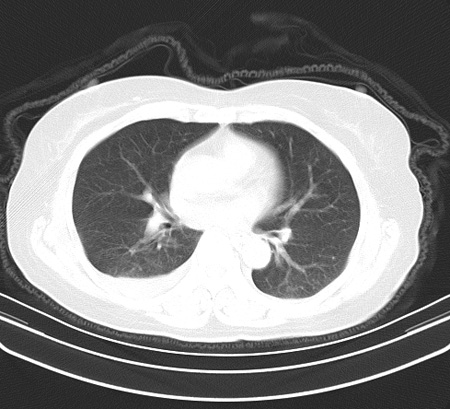

以下是引用余辉在2009-2-19 20:10:00的发言:[br]多考虑急性感染性病变,右中叶尚可见多枚小斑片状影,多为化脓性肺炎,双侧胸腔积液

以下是引用随光逐影在2009-2-19 20:33:00的发言:[br]1)考虑右肺炎症;建议抗炎治疗后复查。2)双侧胸腔积液(以右侧为甚)。

以下是引用花凤凰在2009-2-19 20:46:00的发言:[br]病人有发热,胸痛急性起病,主要病变位于右肺中叶外侧段,呈楔行改变,位于外带胸膜下,考虑为肺梗塞可能!!!!!!!!!!!!!!!!!!!!!!!!!!!!!!!!!!!